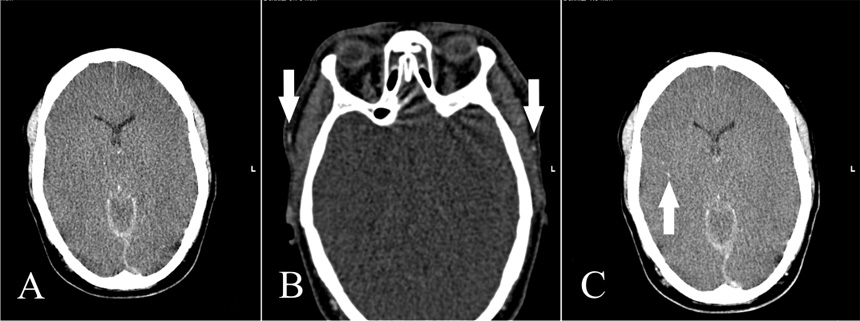

Figure 2

A: Non-contrast CT shows subarachnoid and subdural haemorrhage; gray matter/white matter differentiation is not discernible. B: CTA with contrast media in the superficial temporal artery on both sides indicating a technically sufficient study (white arrows). There is no intracranial arterial opacification. C: Venous-phase CT shows opacification of an M3 segmental artery on the right (white arrow) but no contrast in the M4 segments of the middle cerebral artery and/or the internal cerebral veins. Cerebral circulatory arrest was confirmed.